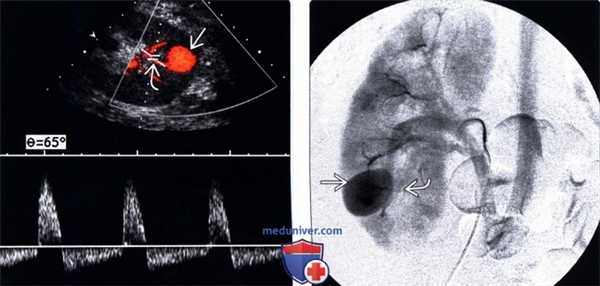

(Левый) На продольном УЗ срезе с допплерографией визуализируется псевдоаневризма в нижнем полюсе трансплантата почки. Характерная синусоидная форма волны в шейке.

(Правый) На цифровой субтракционной селективной артериограмме почки визуализируется псевдоаневризма , заполняющаяся из артерии нижнего полюса . Выполнена эмболизация.